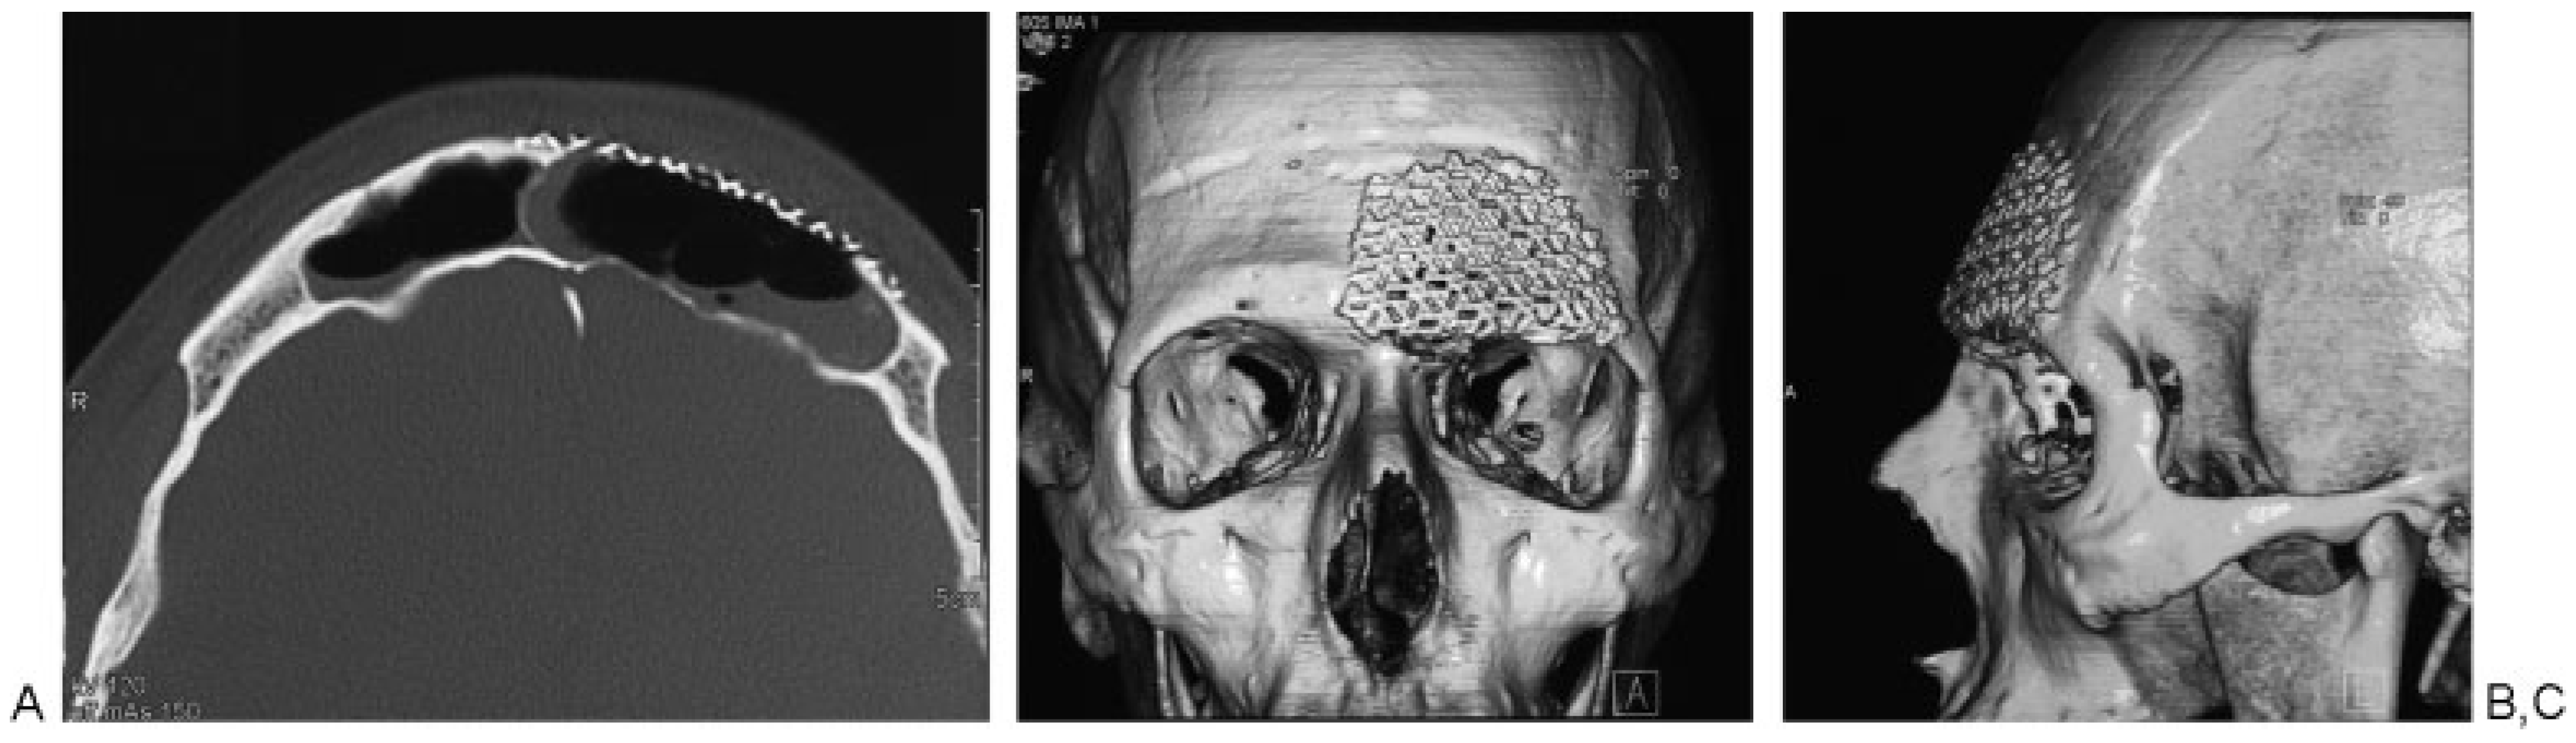

Open Surgical Management of an Asymptomatic Giant Frontal Sinus Osteoma

:Case Report